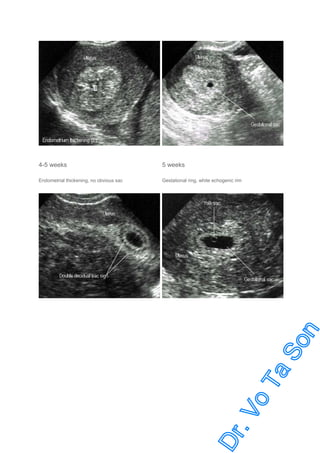

3-4 weeks (after LMP): Endometrial thickenings

4-5 weeks: Gestational sac

5-6 weeks: Yolk sac, double decidual sac sign (DDS)

4-5 weeks

5 weeks

Endometrial thickening, no obvious sac

Gestational ring, white echogenic rim

Double decidual sac sign

Usually seen at 5-6 weeks

Note yok sac